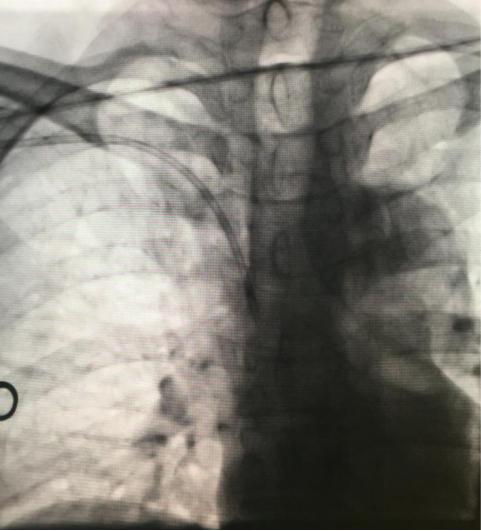

术中透视更有利于确保导管末端位置理想